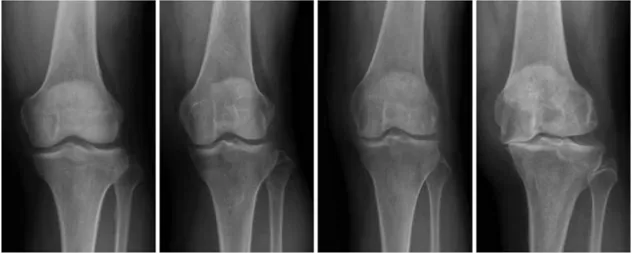

膝骨關節的X-ray分級(從左到右依次為1-4級)

膝骨關節炎是老年人膝蓋疼痛的主要原因。膝關節炎是一個有非常明顯階段性發展的疾病,根據疾病輕重可以分為初期、早期、中期和晚期四個階段。